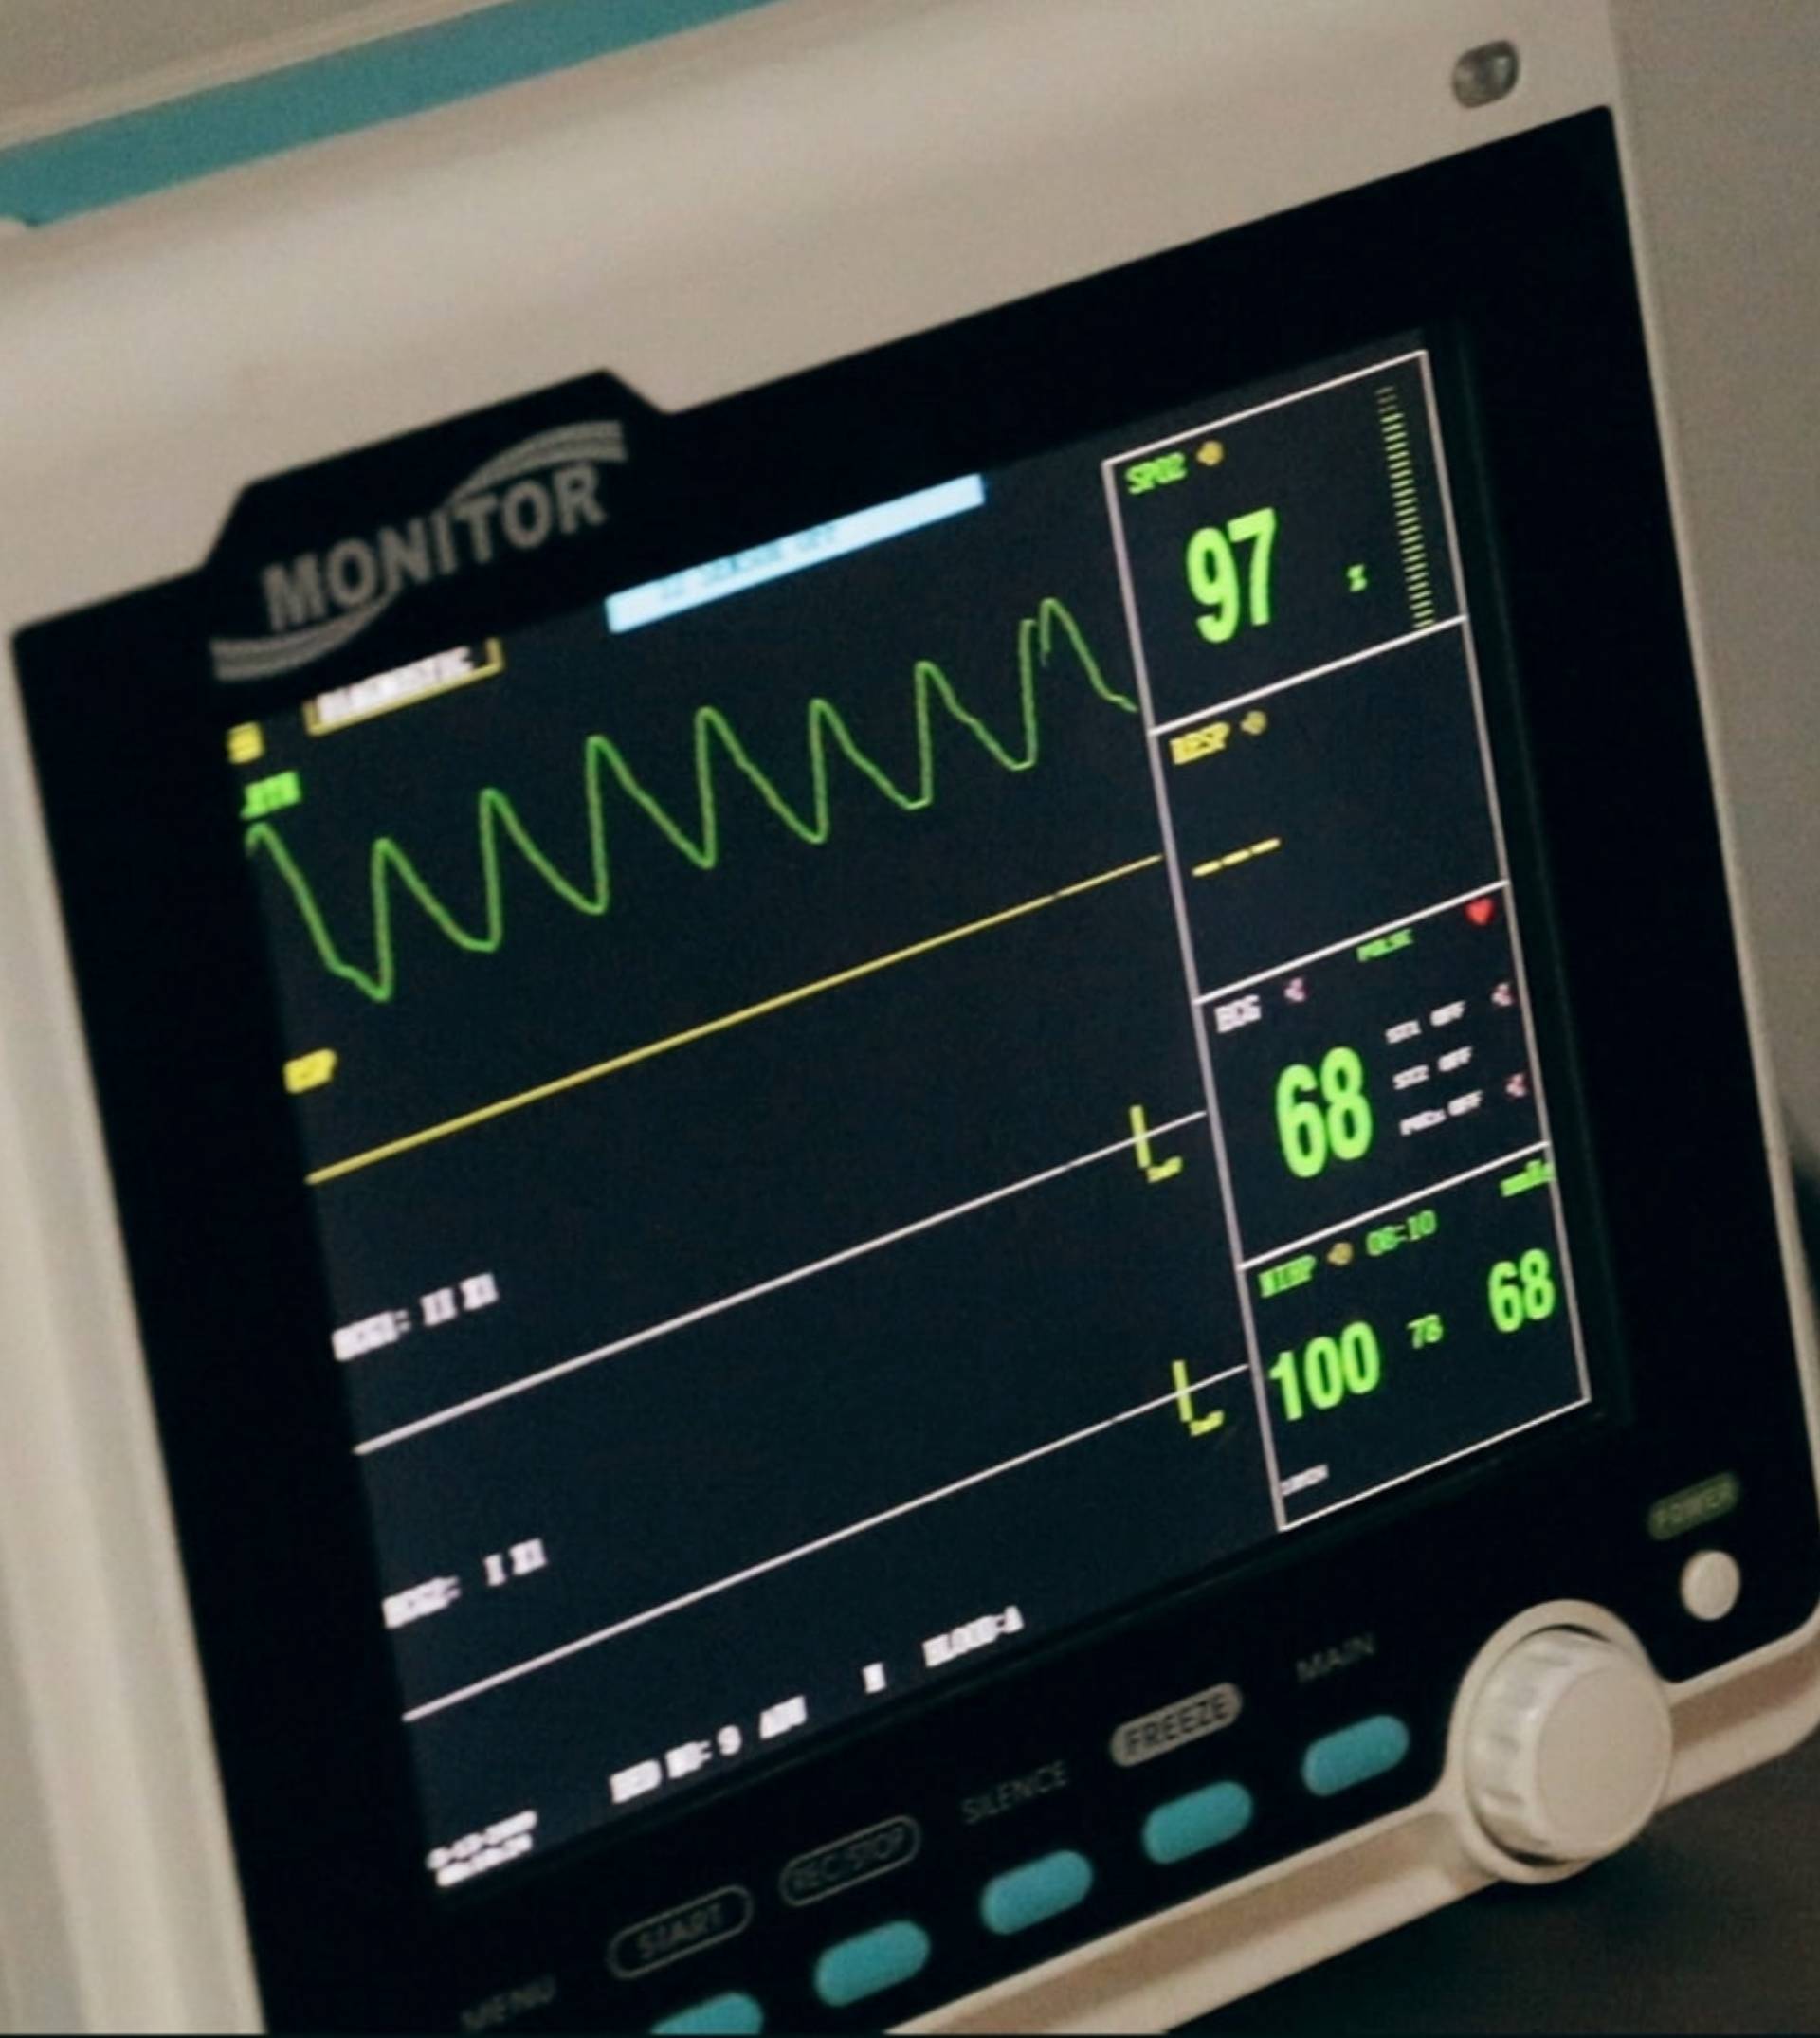

Cardiology